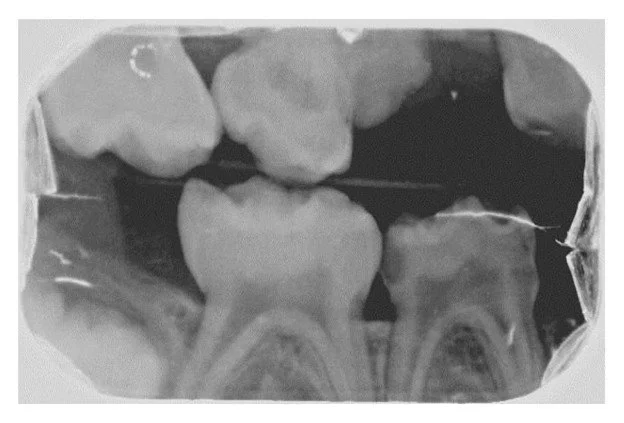

Radiographs confirmed what clinically appeared to be the complete absence of the maxillary left and mandibular right primary canines (63 and 83). Additionally, the right bitewing radiograph showed a suspicious area mesial to the maxillary right first primary molar (Figure 2). A follow-up periapical radiograph of this region was obtained, which demonstrated an unerupted dysmorphic maxillary right primary canine tooth (53) positioned ectopically near the mesial aspect of the maxillary right first primary molar (Figure 3). Upper right and lower left periapical films have atypical presentation distal to the upper right lateral permanent incisors and between permanent lower left canines and lateral incisors. It appears that the tribal leader failed to completely extirpate the developing upper right maxillary primary canine (53), and probably the lower left primary canine (73) due to the continued development of the upper right maxillary primary canine (53) and what appears to be a developing tooth-like remnant on the lower left primary canine area (73) (Figure 4). Additional radiographs confirmed the absence of the maxillary and mandibular left primary canines (Figures 5 and 6). These areas will be followed for the possible formation of supernumerary teeth or odontomas.

Figure 3

This radiograph demonstrates a dysmorphic maxillary right primary canine erupting ectopically into the mesial aspect of the maxillary right first primary molar. This is probably the result of incomplete extirpation by a tribal leader.